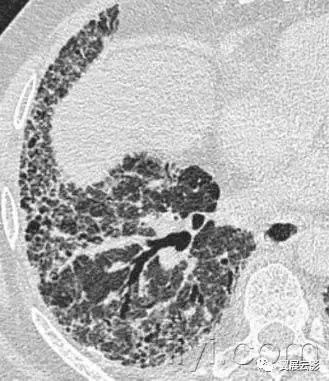

十九、肺实变:

病理学:肺实变是指渗出,或者其他疾病成分替代肺泡内气体,导致肺实变。

平片和CT:肺实变表现为肺实质密度的均匀一致性增高,导致肺血管和气道壁边缘不清。有时可见含气支气管征。只有在极少数的情况下,肺实变的密度变化有助于鉴别诊断,例如脂性肺炎是密度减低,胺碘酮中毒时密度增高。

图示为多灶性的肺实变。